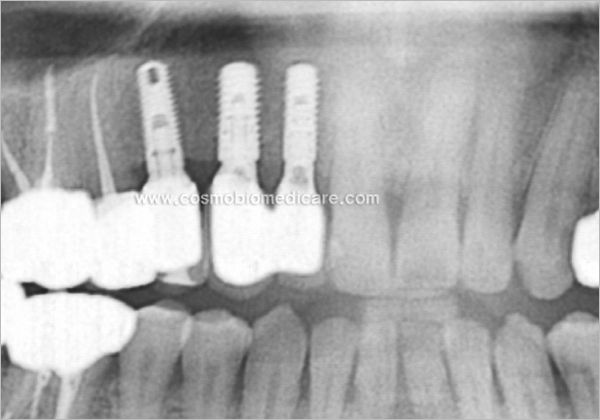

Clinical Cases

• Case1

• Case2

• Case3

• Case4

• Case5

• Case6

• Case7

• Case8

• Case9

• Case10